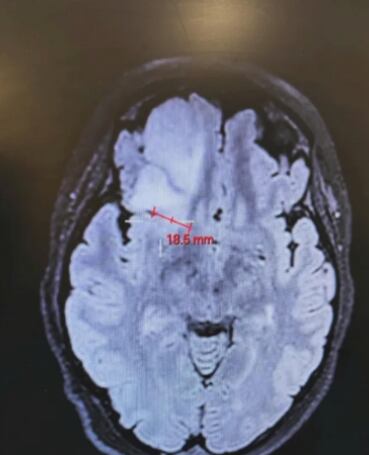

Sin embargo, con el resultado de la tomografía computarizada descubrieron que la mujer de 26 años se enfrentaba a un tumor cerebral de 6 centímetros. Si bien fue tratada con quimioterapia, los médicos no son optimistas: le diagnosticaron pocos años de vida.

Tras el nacimiento de su bebé, la mujer se sometió a una cirugía, donde pudieron eliminar el 85% del tumor, pero en su lóbulo frontal derecho quedó alojado un 15% restante.

Luego de la cirugía, pudieron determinar que Bethany tenía un astrocitoma de grado 3, un tumor agresivo de rápido crecimiento en el sistema nervioso central.